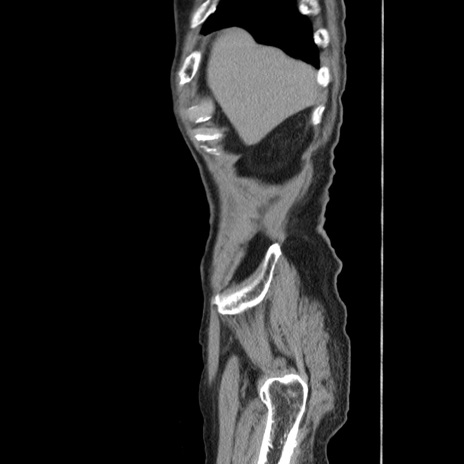

症例24(矢状断像)

【症例】80歳代男性

【主訴】左側腹部痛、嘔吐

【現病歴】本日早朝より左腹部に痛みあり。昼頃嘔吐認めたため、救急要請。

【既往歴】直腸癌(Mile手術)、胆摘

【身体所見】意識清明、BT 35.9℃、BP 221/93mmHg、SpO2 97%(RA) 、腹部:左ストーマ周囲に限局性の腹部膨隆あり。 膨隆部自発痛・圧痛あり・軟。